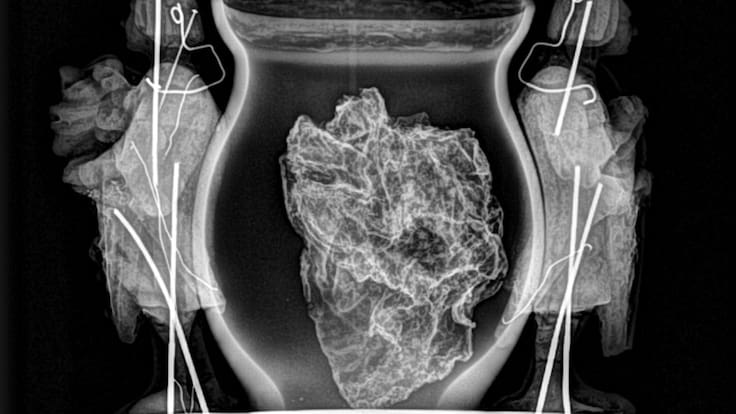

"Las pruebas que hemos hecho hasta el momento son un tac, una radiografía, tanto de la caja como del corazón y hemos tomado muestras que todavía no están analizadas porque la mayor parte de los análisis que se van a hacer son PCRs y ahora no están disponibles los instrumentos", dice Alicia Ancho, técnica restauradora y jefa de la Sección de Registro, Bienes Muebles y Arqueología.